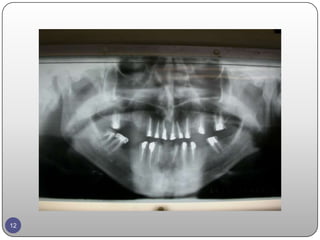

Points taken inconsideration.  In complicated cases temporary restoration should be done to reach a satisfactory esthetic and functional permanent restoration.  Ten years success rate is about 95% for an implant. A tooth with RCT + parapost with crown has 90% success for ten years.  The bio mechanic principles of FPD.  The strategic teeth.  Treatment of complicated cases is the result of cooperation between the different dental specialties.  Treatment planning. 10